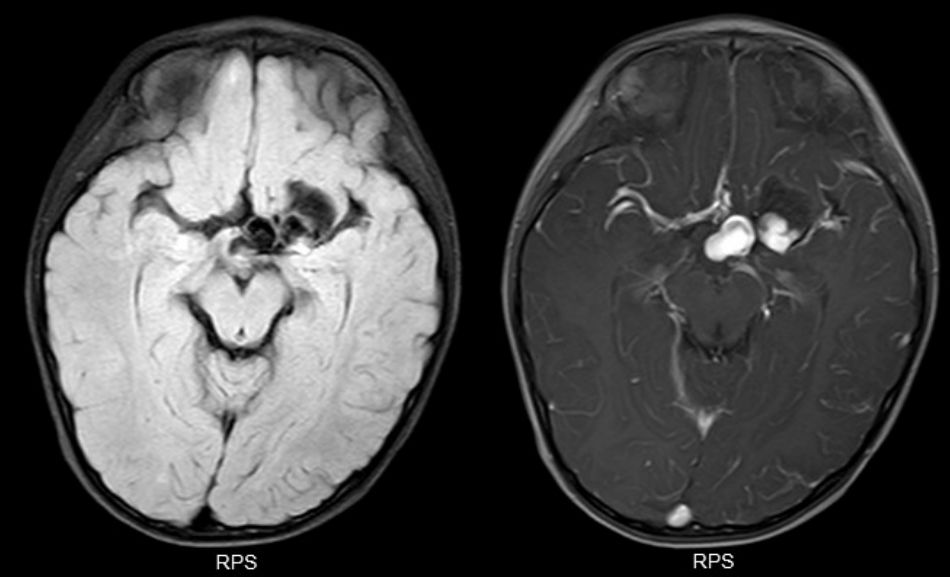

查头颅MRI提示:左侧鞍上可见两处结节状异常信号影,病变内信号不均匀,周围可见扭曲血管流空影,增强后明显强化,血管畸形伴出血可能(图2)。

图2. MRI提示鞍上及外侧裂区多发类圆形结节病灶,强化明显,边界清。